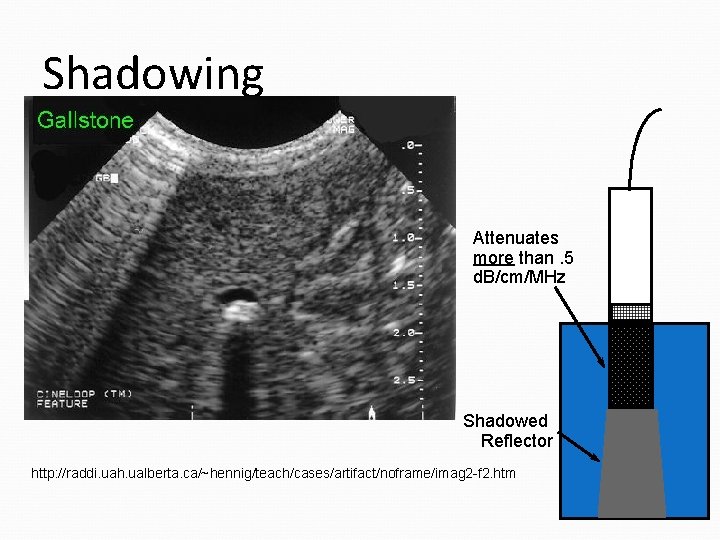

Shadowing Clinical Manifestation reduction in imaged reflector amplitude Cause object between this reflector & transducer attenuates ultrasound more than assumed compensation not enough to provide proper signal amplitude intensity under-compensated Attenuates more than. 5 d. B/cm/MHz Opposite of Enhancement Shadowed Reflector

Shadowing Attenuates more than. 5 d. B/cm/MHz Shadowed Reflector http: //raddi. uah. ualberta. ca/~hennig/teach/cases/artifact/noframe/imag 2 -f 2. htm